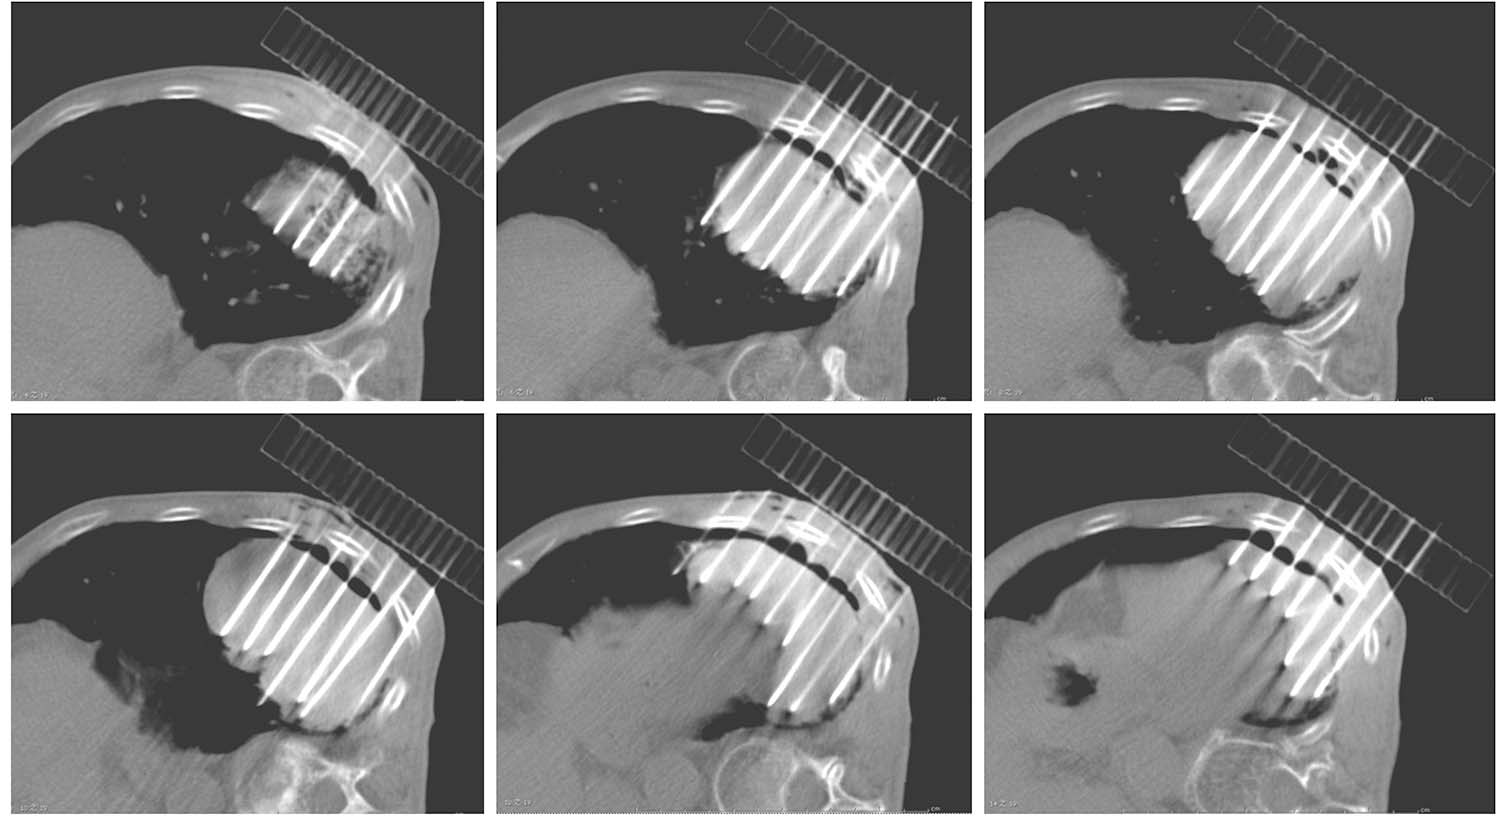

患者取与术前CT扫描相同体位,真空负压垫固定体位,防止穿刺过程中因体位变动给穿刺带来的不利影响。将导航支架与CT碳纤维床板相连接,以0.5cm层厚扫描,选取病灶中心层面,将一个预定进针点在皮肤表面做出大十字标记,消毒、铺巾、局麻,安装模板,用激光灯校准模板,使激光灯的 x 轴和 y 轴投影与模板表面的标记线相重合,利用数字化角度仪或者水平仪调整模板的角度和方向,使模板在 y 轴方向的角度为零,调整 x 轴方向的角度,与术前计划保持一致。选择病灶中心层面,参考术前计划,将数根穿刺针抵达皮肤表面,扫描观察针尾走行方向,再次校准模板,然后测量进针的深度,完成该层面的进针,如果是肺等移动度较大的脏器,可以先插入2~3根固定针,将病灶与模板迅速“绑定”(图4-3-1),然后再依次完成其他层面的进针,如果遇到坚韧骨骼遮挡,使用捻针或骨钻打孔技术破骨插植,待完成所有层面的进针以后再植入粒子。

图4-3-1 进针过程

例1 患者男性,72岁,左肺鳞癌侵犯胸壁并同侧肺门淋巴结转移,T4N1M0。2018年1月16日行共面模板引导放射性粒子植入术(图4-3-2~图4-3-7)。

图4-3-3 模板引导,完成选择层面的进针

图4-3-4 依次完成其他层面的进针

图4-3-5 完成肺门病灶的进针

图4-3-6 完成肺门病灶的粒子植入